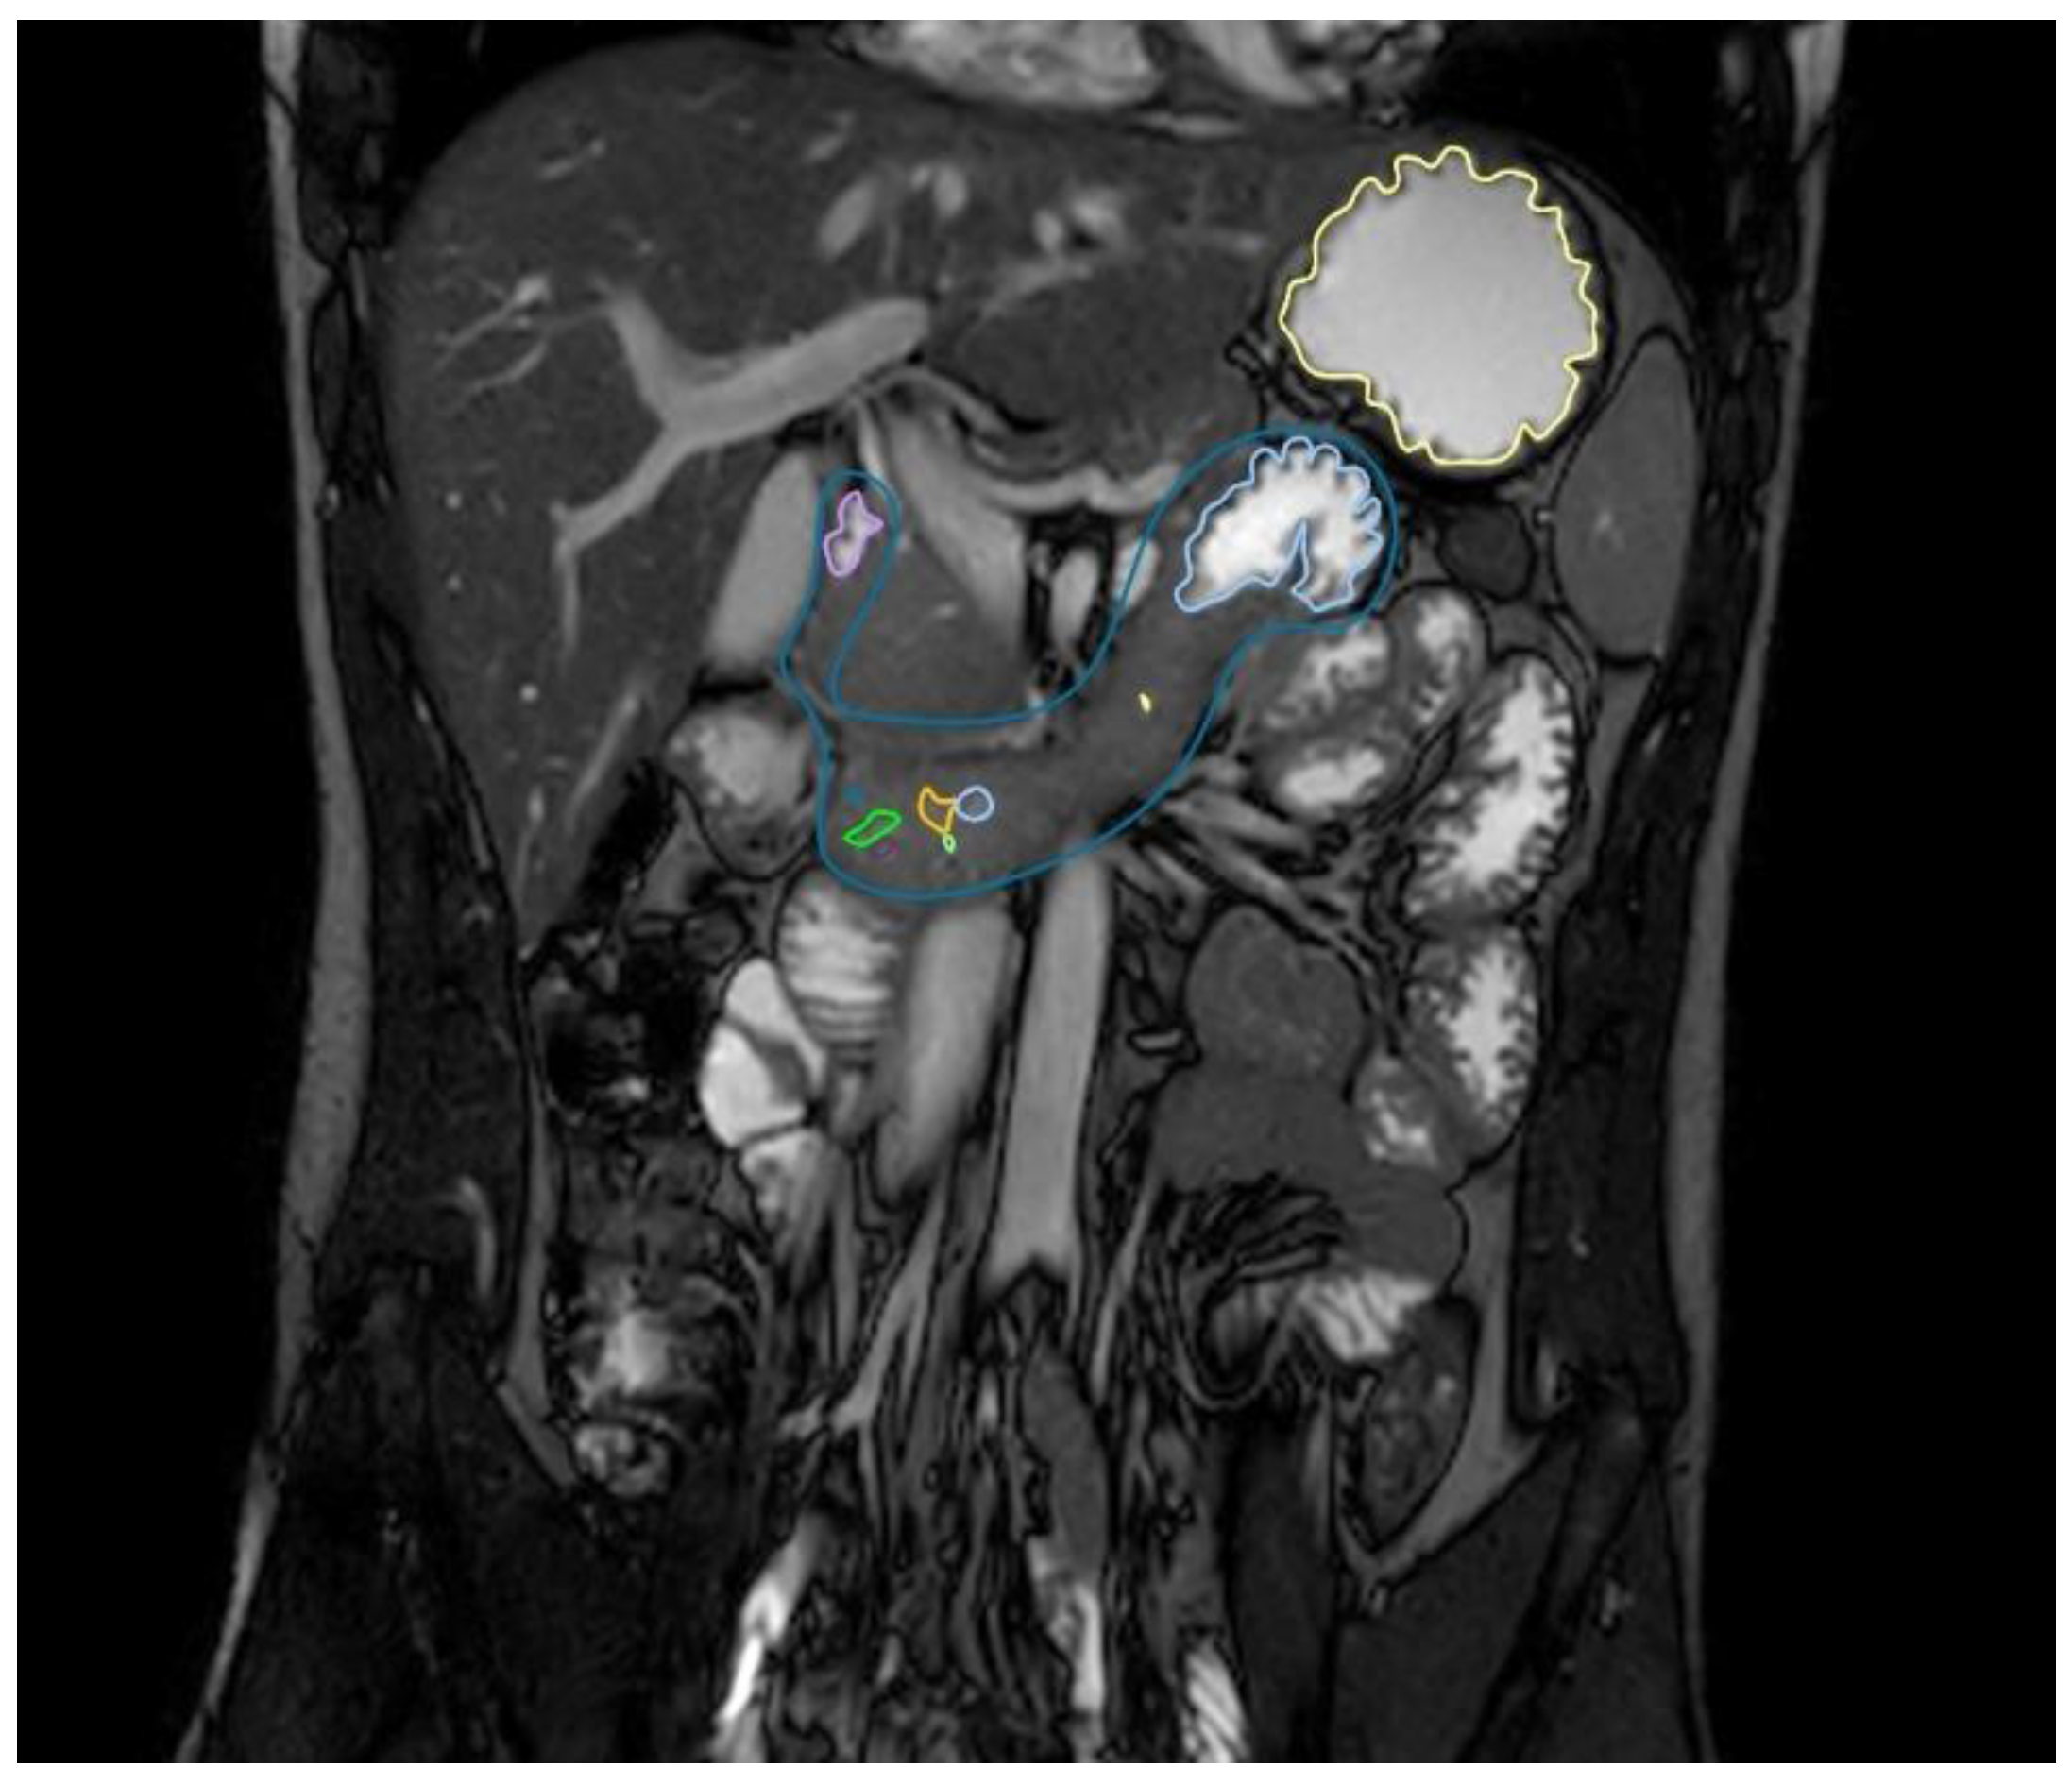

2.2.3. Gastric and Duodenal Fluid Volume via MRI

| Type | T2-weighted turbo spin-echo | T2/T1 TrueFISP | T2-weighted turbo spin-echo |

| Plane | Coronal | Coronal | Axial |

| Repetition time (ms) | 591.75 | 4.83 | 579.66 |

| Echo time (ms) | 120 | 2.41 | 120 |

| Acquisition matrix | 344 · 300 | 328 · 329 | 288 · 250 |

| Slice thickness (mm) | 4 | 4 | 4 |

| Interslice gap (mm) | 0.6 | 0 | 0.6 |

| Number of averages | 1 | 1 | 1 |

| Acquisition time (s) | 23.67 | 18.45 | 22.57 |